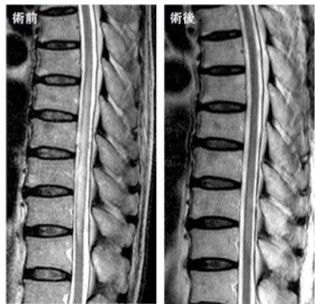

脊髄動静脈奇形 術前と胸椎後方到達法による直達手術後